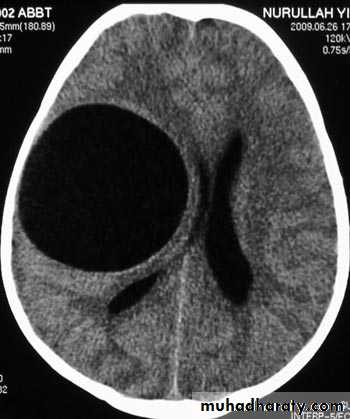

Hydrocephalous

2 types

Obstructive ( non – communicating )

Craniophyrengioma

Medulloblastoma

Ependymoma

Aquiduct stenosis , comments cause of obstruction being congenital in nature .

Non –obstructive ( communicating )

No obstruction of the ventricular pathway , but the absorption of the csf at the level of arachnoids' granulation is occluded secondary to lodge by blood clot or inflammatory cell or infection post meningitis most commonly to occur post SAH .